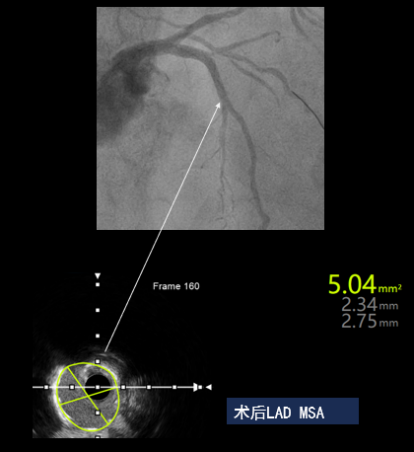

首先对前降支进行功能性评估,QFR值为0.67,拟对前降支分叉病变进行处理。患者为低体重女性,前降支近段、中段弥漫病变,陈淮沁教授通过IVUS精准选择了2.5*20mm药物涂层支架,并在近段使用3.0*8mm进行后扩张,最终减少了支架植入,术后LAD QFR值0.90。